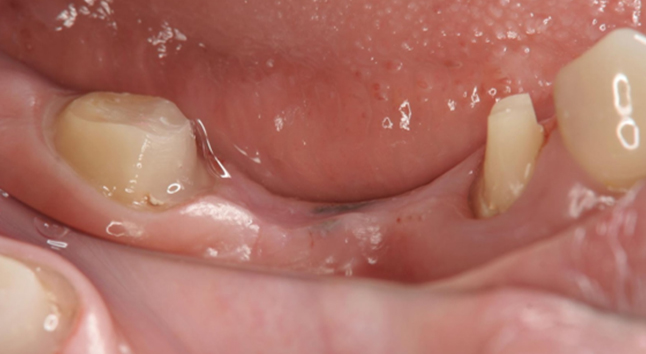

まず悪くなった歯を抜歯をして、2週間ほど歯茎が回復するのを待ちました

その後、骨にインプラントを埋めて、6週間後に歯型を取りセラミックの歯を作成、更にインプラント部位(赤丸部分)の前後の歯もセラミックで作成し装着しています。